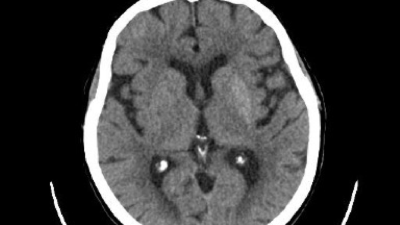

Third ventricle hydatid cyst in a 4-year-old

A 4-year-old presented with right-eye strabismus, headache, and vomiting. Imaging revealed third-ventricle hydatid cyst causing hydrocephalus. Neuroendoscopic excision and histology confirmed hydatid disease, successfully treated with albendazole.

Radiologist looking at MRI scan of the head/© simonkr / Getty Images / iStock (symbolic image with models), Female doctor talking to male patient/© FatCamera / Getty Images / iStock (symbolic image with models), Wolf portrait/© Ranjie Cabelin / 500px / Getty Images, DNA helix with red spot/© Елена Бутусова / Stock.adobe.com, Flow diagram/© narvo vexar / Getty Images / iStock, Human brain illustration/© (M) CHRISTOPH BURGSTEDT / SCIENCE PHOTO LIBRARY / Getty Images, Emergency ambulance transfer/© Ronny / stock.adobe.com, Lab technician checking blood sample/© FatCamera / Getty Images / iStock (symbolic image with model), Older woman wearing a continuous glucose monitoring device/© Halfpoint / stock.adobe.com (symbolic image with model), MRI of a third ventricle hydatid cyst in a 4-year-old female/© 2025, Ahed Assaf et al, J Med Case Reports, Illustration of varicella zoster virus/© quantic69 / Getty Images / iStock, Medicine Matters Podcast promo image/© Springer Medizin GmbH, Navigating neuroimaging in Alzheimer’s care: Practical applications and strategies for integration/© Springer Health+ IME, Alzheimer’s disease in the biomarker era: preparing the multidisciplinary care team/© Springer Healthcare IME, Awareness, Advances, and Action: Optimizing Outcomes for Patients With Generalized Myasthenia Gravis/© Springer Healthcare IME, Woman holding head/© Tero Vesalainen / Getty Images / iStock (symbolic image with model), Neurological stenting concept/© freshidea / stock.adobe.com, MRI-guided laser interstitial thermal therapy/© ATRPhoto / Stock.adobe.com, Senior adults walking/© Alistair Berg / Getty Images (symbolic image with models), Amyloid-beta peptide accumulating into amyloid fibrils/© selvanegra / iStock / Getty Images Plus, Older man trying to sleep/© amenic181 / Getty Images / iStock (symbolic image with model), Brain inside a medicine capsule/© Jorg Greuel / Getty Images, Man undergoing an EEG/© fotografixx / Getty Images / iStock (symbolic image with model), Doctors discussing brain scans and treatment decisions/© dragana991 / Getty Images (symbolic image with models), Head with heart and cardiogram/© sewcream / stock.adobe.com, Neurologist examining MRI brain scan/© Gorodenkoff / stock.adobe.com (symbolic image with model), Epilepsy concept image/© SewcreamStudio / Stock.adobe.com, Neuromodulation concept/© ArtemisDiana / Getty Images, Cluster headache concept/© Prostock-studio / Stock.adobe.com (symbolic image with model), Woman speaking to doctor/© Seventyfour / stock.adobe.com (symbolic image with models), Boy with headache lying on a bed/© Pollyana Ventura / Getty Images / iStock (symbolic image with model), Teratoma of the fallopian tube in a patient with autoimmune encephalitis/© 2025, María Rivera Sánchez et al, BMC Neurol, Lumbar puncture to extract CSF/© Felipe Caparrós / stock.adobe.com, Aspergillus fungus in a Petri dish/© sinhyu / Stock.adobe.com, Deer tick Ixodes Ricinus/© KPixMining / stock.adobe.com, 3D illustration of a brain tumor/© (M) SciePro / stock.adobe.com, Pills on background of brain MRI scan/© Ildar Imashev / Getty Images / iStock, DNA editing illustration/© (M) vchalup / stock.adobe.com, Hemifacial spasm/© 2023, David Aktan et al under exclusive licence to Belgian Neurological Society, Acta Neurol Belg, A middle-aged man grimacing/© Aflo Images / Getty Images (symbolic image with model), Close-up of doctor examining a foot with a bandage/© megaflopp / Getty Images / iStock, Older man having trouble sleeping/© Enes Evren / Getty Images / iStock (symbolic image with model), Peripheral nerve histology: bundles of myelinated axon fibers/© 2rogan / Generated with AI / Stock.adobe.com